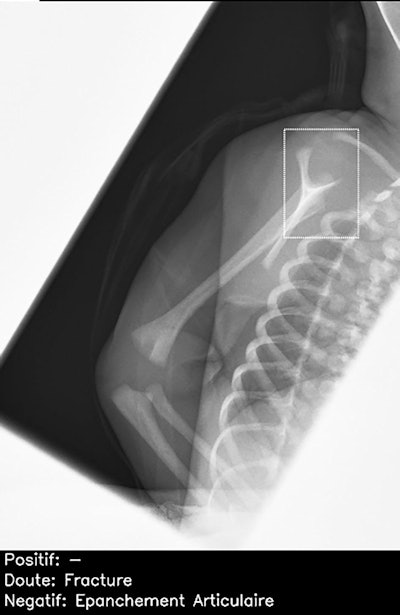

Normal lateral scapular Y view of right shoulder in child, incorrectly interpreted by AI candidate as having proximal humeral fracture (dashed bounding box). This was a false-positive result, which was correctly identified as normal by all 26 radiologists. Note: épanchement articulaire = joint effusion.Further training of the AI product is needed, particularly for cases considered "noninterpretable," such as abdominal radiographs and those of the axial skeleton, they said.